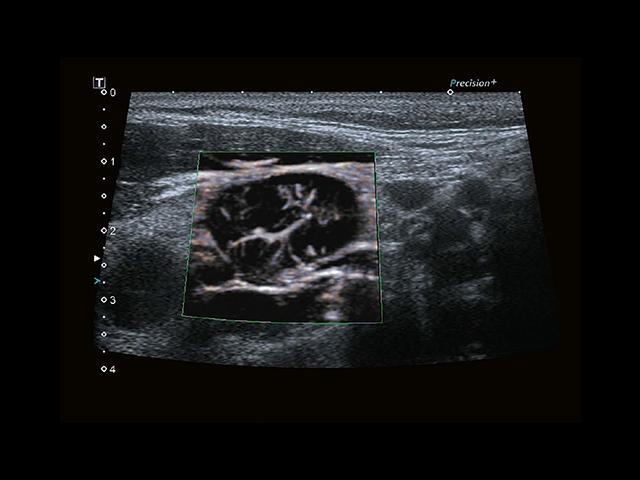

Aplio 500 – ультразвуковой сканер премиум класса, сочетающий в себе быстродействие диагностики и отличное качество визуализации. Более 30 датчиков на выбор, в т.ч. матричные, монокристаллические, 4D, эндоскопические для любых типов исследований. Ультразвуковой сканер позволяет изучать анатомические структуры в высоком разрешении.

Обновленная версия легендарного УЗ-сканера. Стационарный аппарат экспертного класса Aplio 500 Toshiba NEW, визуализирует анатомические структуры в высоком разрешении. Модель позволяет выявить микрокальцификаты, новообразования, нарушения в работе сердца, сосудов и мышц. Присутствует функция виртуальной эндоскопии, 4D-сканирования, эластометрии тканей, УЗИ с контрастированием. За повышение качества изображения отвечают технологии ApliPure и Superb Microvascular Imaging. Первая задействует возможности пространственного и частотного кодирования, формирует цельный визуальный ряд с сохранением клинических маркеров. Вторая улучшает отображение микрососудистого русла, используя доплеровский эффект. Модель оснащена 21-дюймовым монитором, имеет 4 активных порта. Возможно подключение педиатрических, интраоперационных, лапароскопических и чреспищеводных датчиков.

• SMI. Опция, упрощающая визуализацию микроциркуляторного русла. С ее помощью обследуются сосуды с низкой интенсивностью кровотока, изучаются наиболее тонкие структуры. SMI упрощает диагностику новообразований, минимизирует вероятность ошибки.